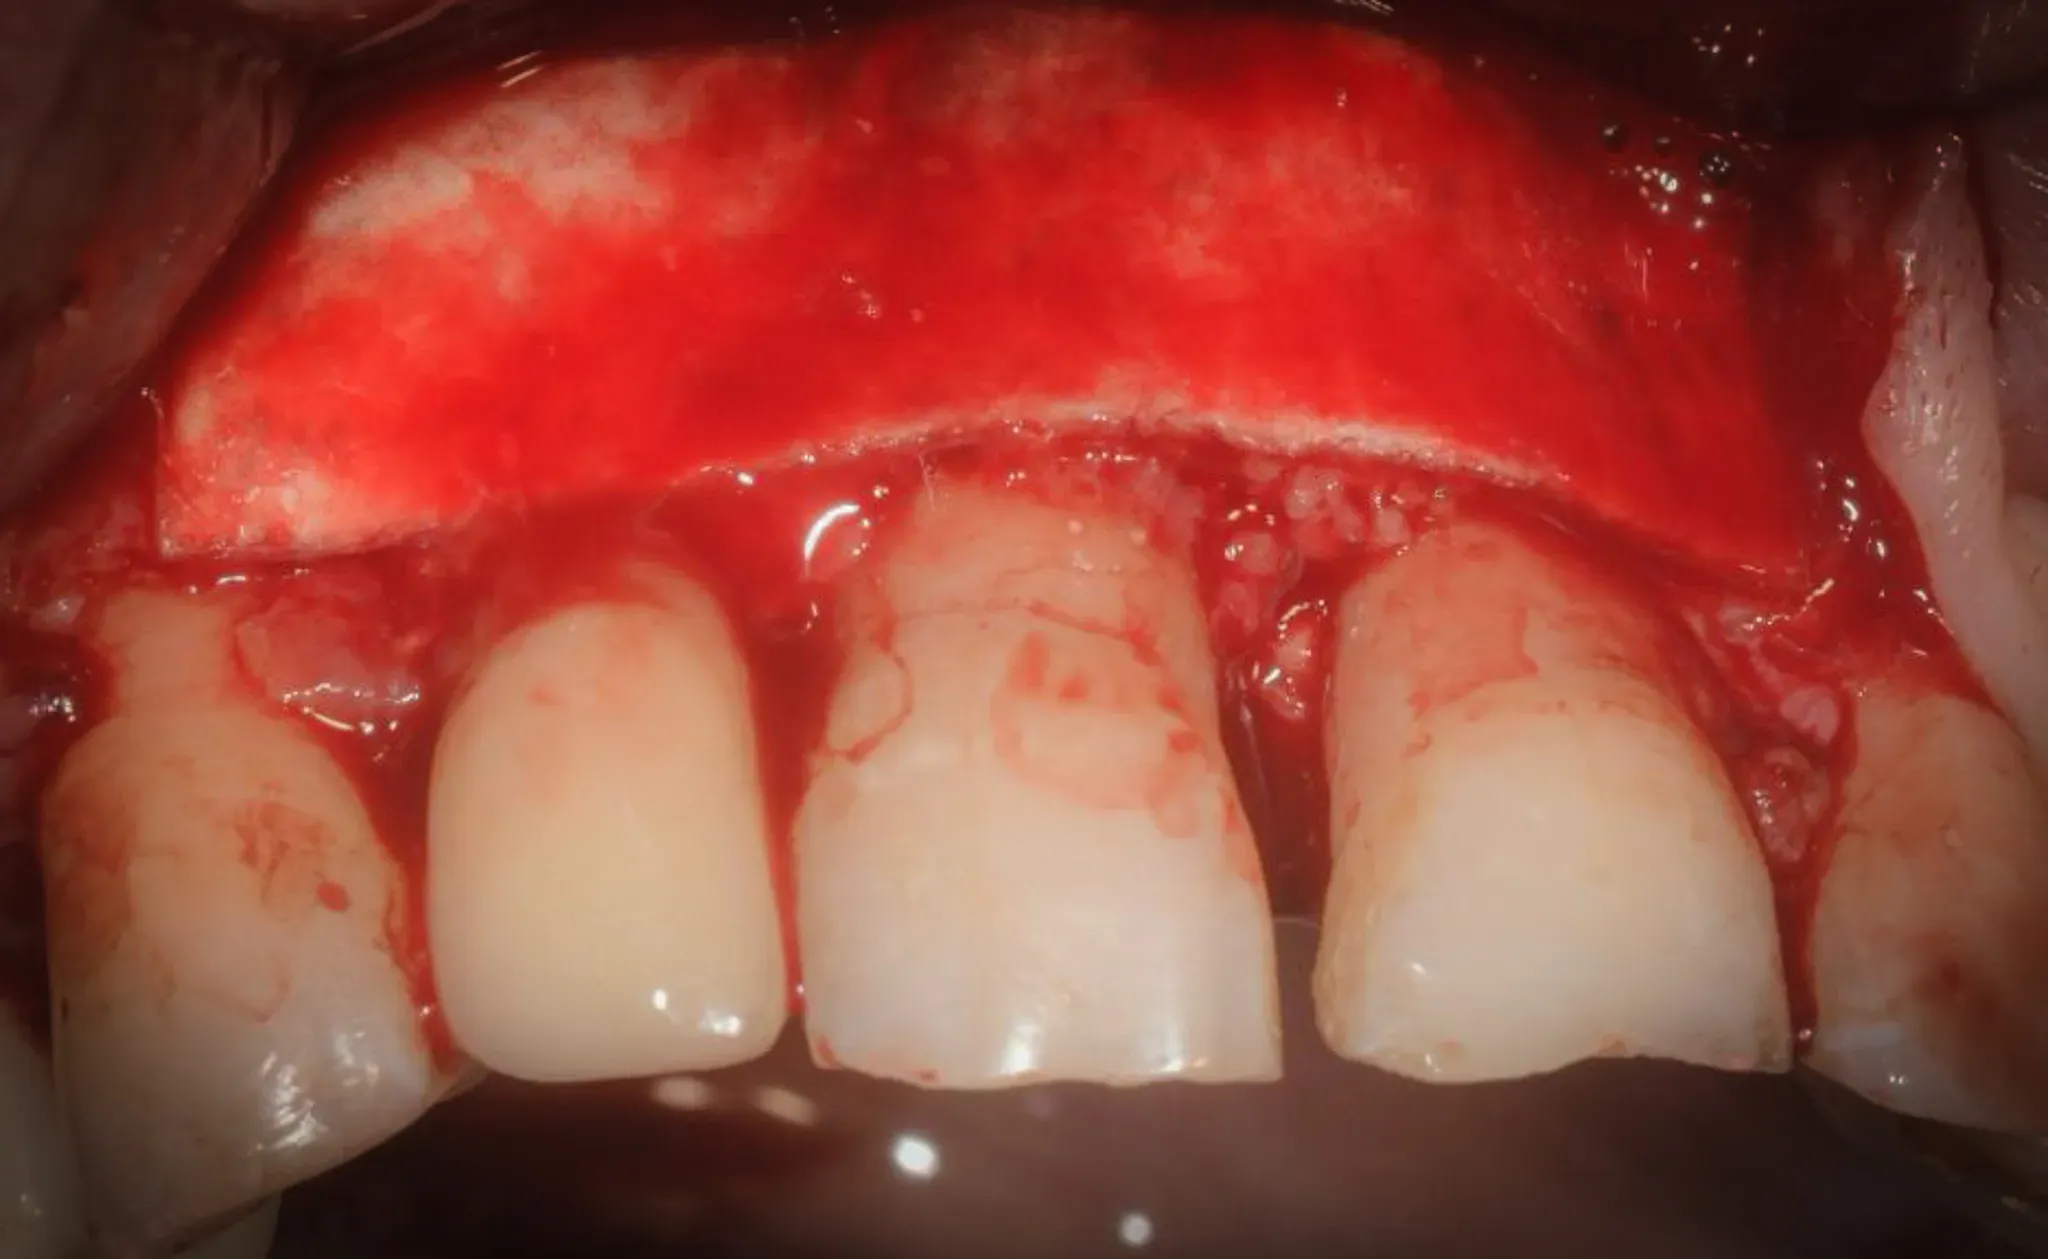

As coverage: a 0.5 mm porcine cortical bone lamina, serving as a semi-rigid barrier. Its role is twofold — space maintenance and protection of the underlying clot. Not a conventional resorbable membrane, but a structure offering mechanical resistance during the weeks when soft tissue tends to collapse into the defect.

The cortical lamina is also stabilised with fibrin glue.